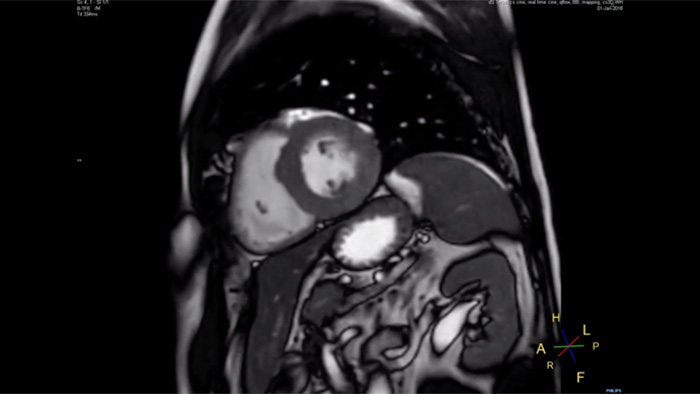

Philips Compressed SENSEを使用すると、MR検査時間を短縮できます。さらに、Compressed SENSEでは息止め時間を短縮できるため、MR検査の質を向上させることができます。

息止め時間、4.8秒

患者にとって息止め時間が短い方が負担が少なく、息止めの失敗が大幅に減少します。

当院では、心臓MRに必要な息止め回数や息止め時間を減らすことができました」

小山貴医師、博士(医学)、放射線診断医、放射線診断科主任部長、放射線センター長、倉敷中央病院

15~16秒におよぶ息止め時間は、心疾患患者にとって苦痛となることがあります。Compressed SENSEには、息止め時間10秒未満のプロトコルが実際に搭載されています。息止め時間が短いほうがはるかに楽なので、検査の満足度が大幅に向上します」

Trevor Andrews博士、MR技師、バーモント大学メディカルセンター、米国